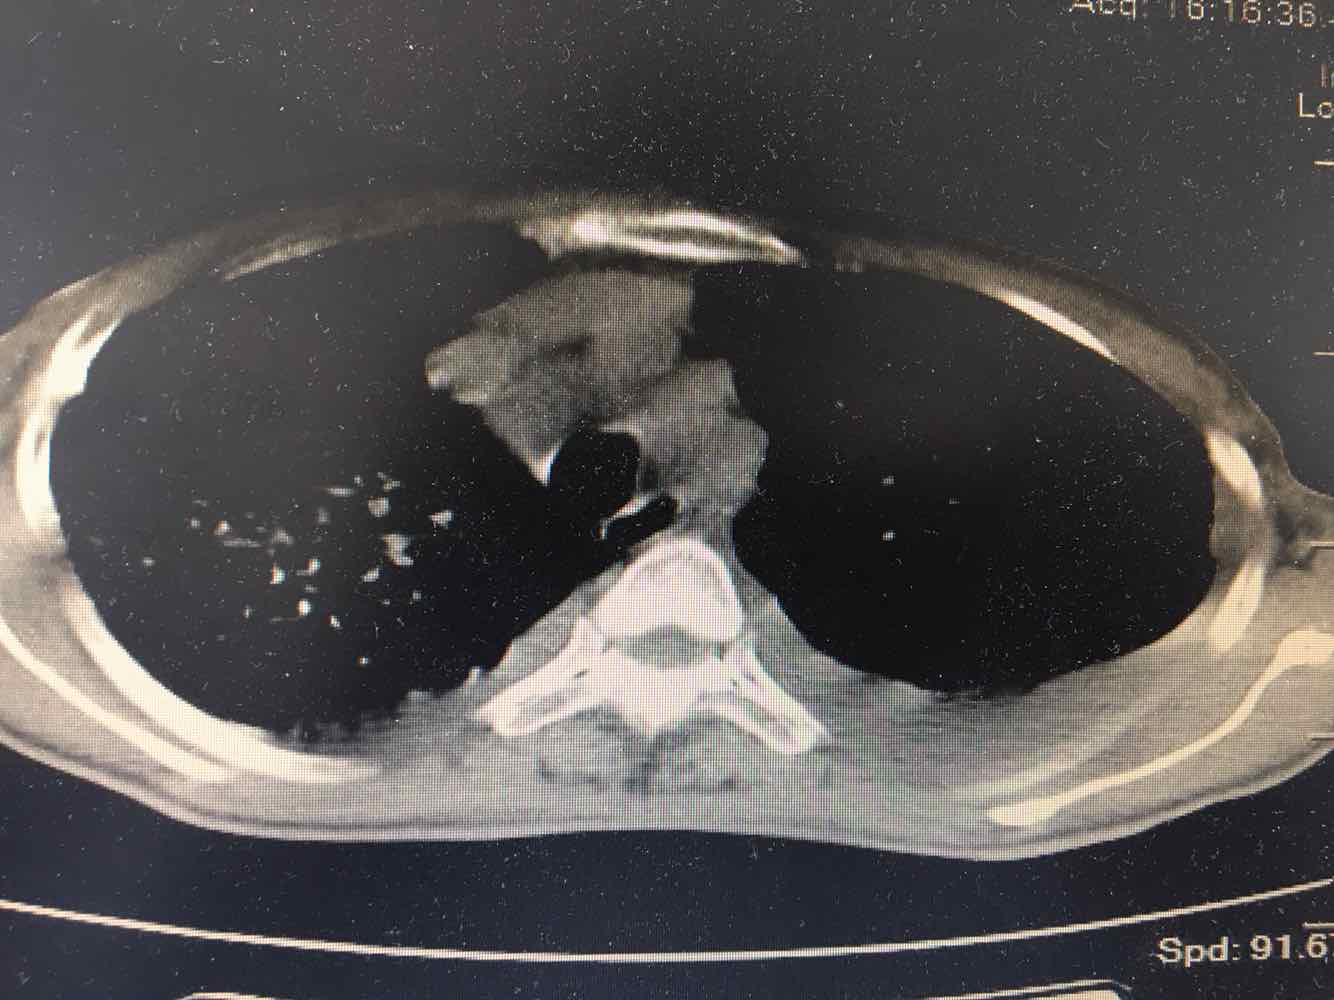

女,51岁,支气管扩张病史多年。慢性咳嗽咳痰喘息30年,加重1个月,无发热,气短为主,痰液不多,上腹不适,少尿。双肺干湿罗音。